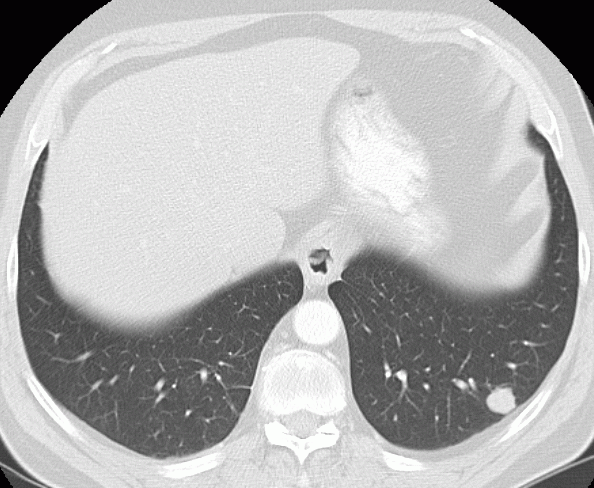

![]() | 69-jähriger Mann mit adenopapillärem Ösophaguskarzinom.![]() | |